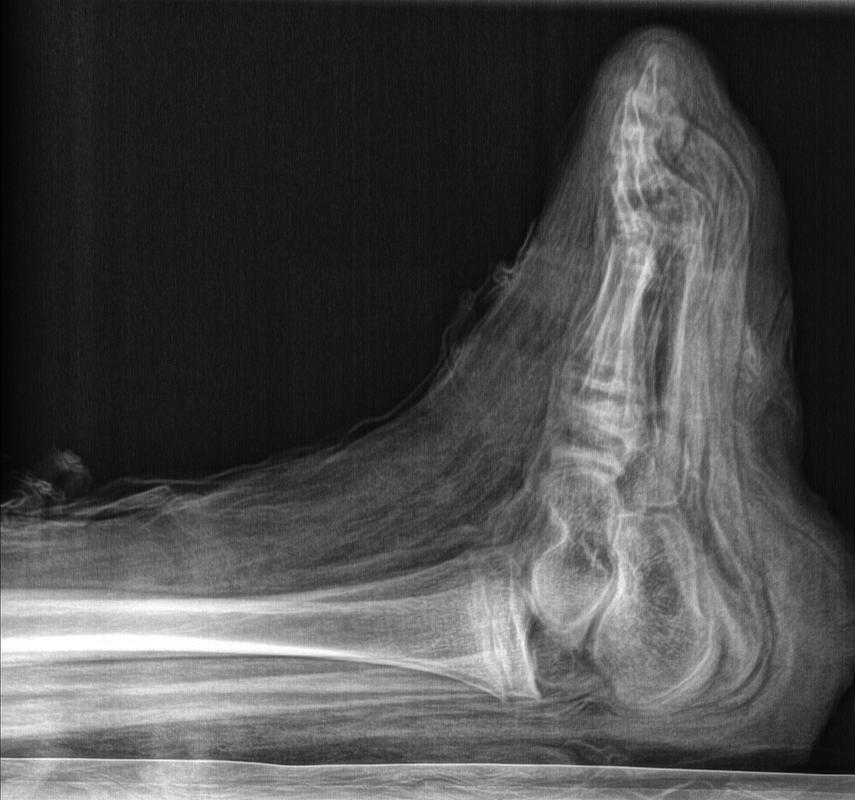

mummy, boy, human remains

- The mummy of a small boy.